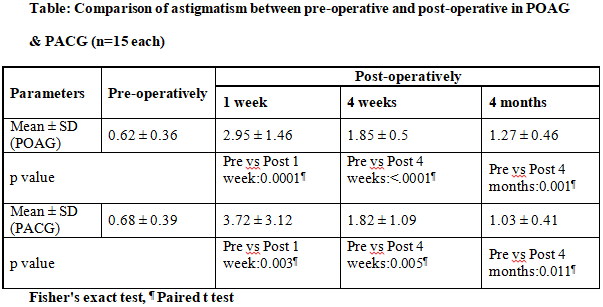

Comparison of astigmatism in both groups is shown in table

There was no statistically significant difference between 2 group (p=0.15).

post-trabeculectomy predictors of bleb outcome(17,18). Low reflectivity of bleb wall, presence of posterior episcleral fluid have been associated with lower IOP(14,16). Astigmatism increased at 1week postoperative period in both

groups and remained at 4 weeks despite removal of releasable sutures. Tear film disruption was noted. There were improved TBUT readings over time, but residual TBUT reduction remained till 4 months. Intergroup difference at all

times was NS in both groups.